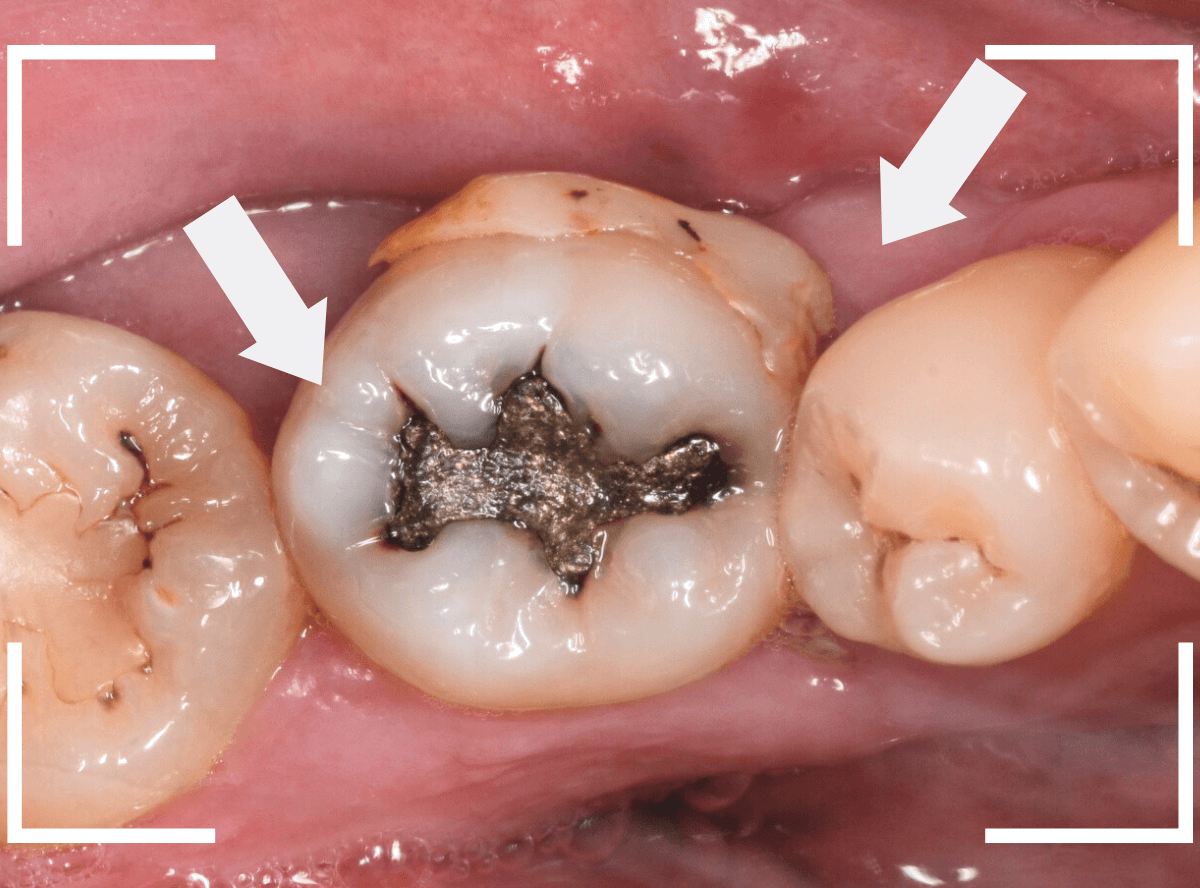

Case.11 劣化したレジンの下で虫歯

今回は、レジンの中の虫歯の話です。

以前に治療をしたレジンが劣化して変色し、中も黒くぼやっと見えます。

このような状況では、治療をすると大きな虫歯が見つかる事が多いです。

レントゲン写真で確認します。

レントゲン写真だけでは、虫歯のようには見えません。

患者さんに状況を説明し、レジンを外して中を調べると、大きな虫歯が見つかりました。

虫歯治療を進めると、まだまだ虫歯が出てきます。

想像以上に大きな虫歯です。

慎重に虫歯を全て除去しました。

神経まで達した虫歯の可能性も頭をよぎりましたが、なんとかその寸前で食い止められ、ほっとしました。

しばらくはお薬をつめて,症状が出ないか経過観察します。